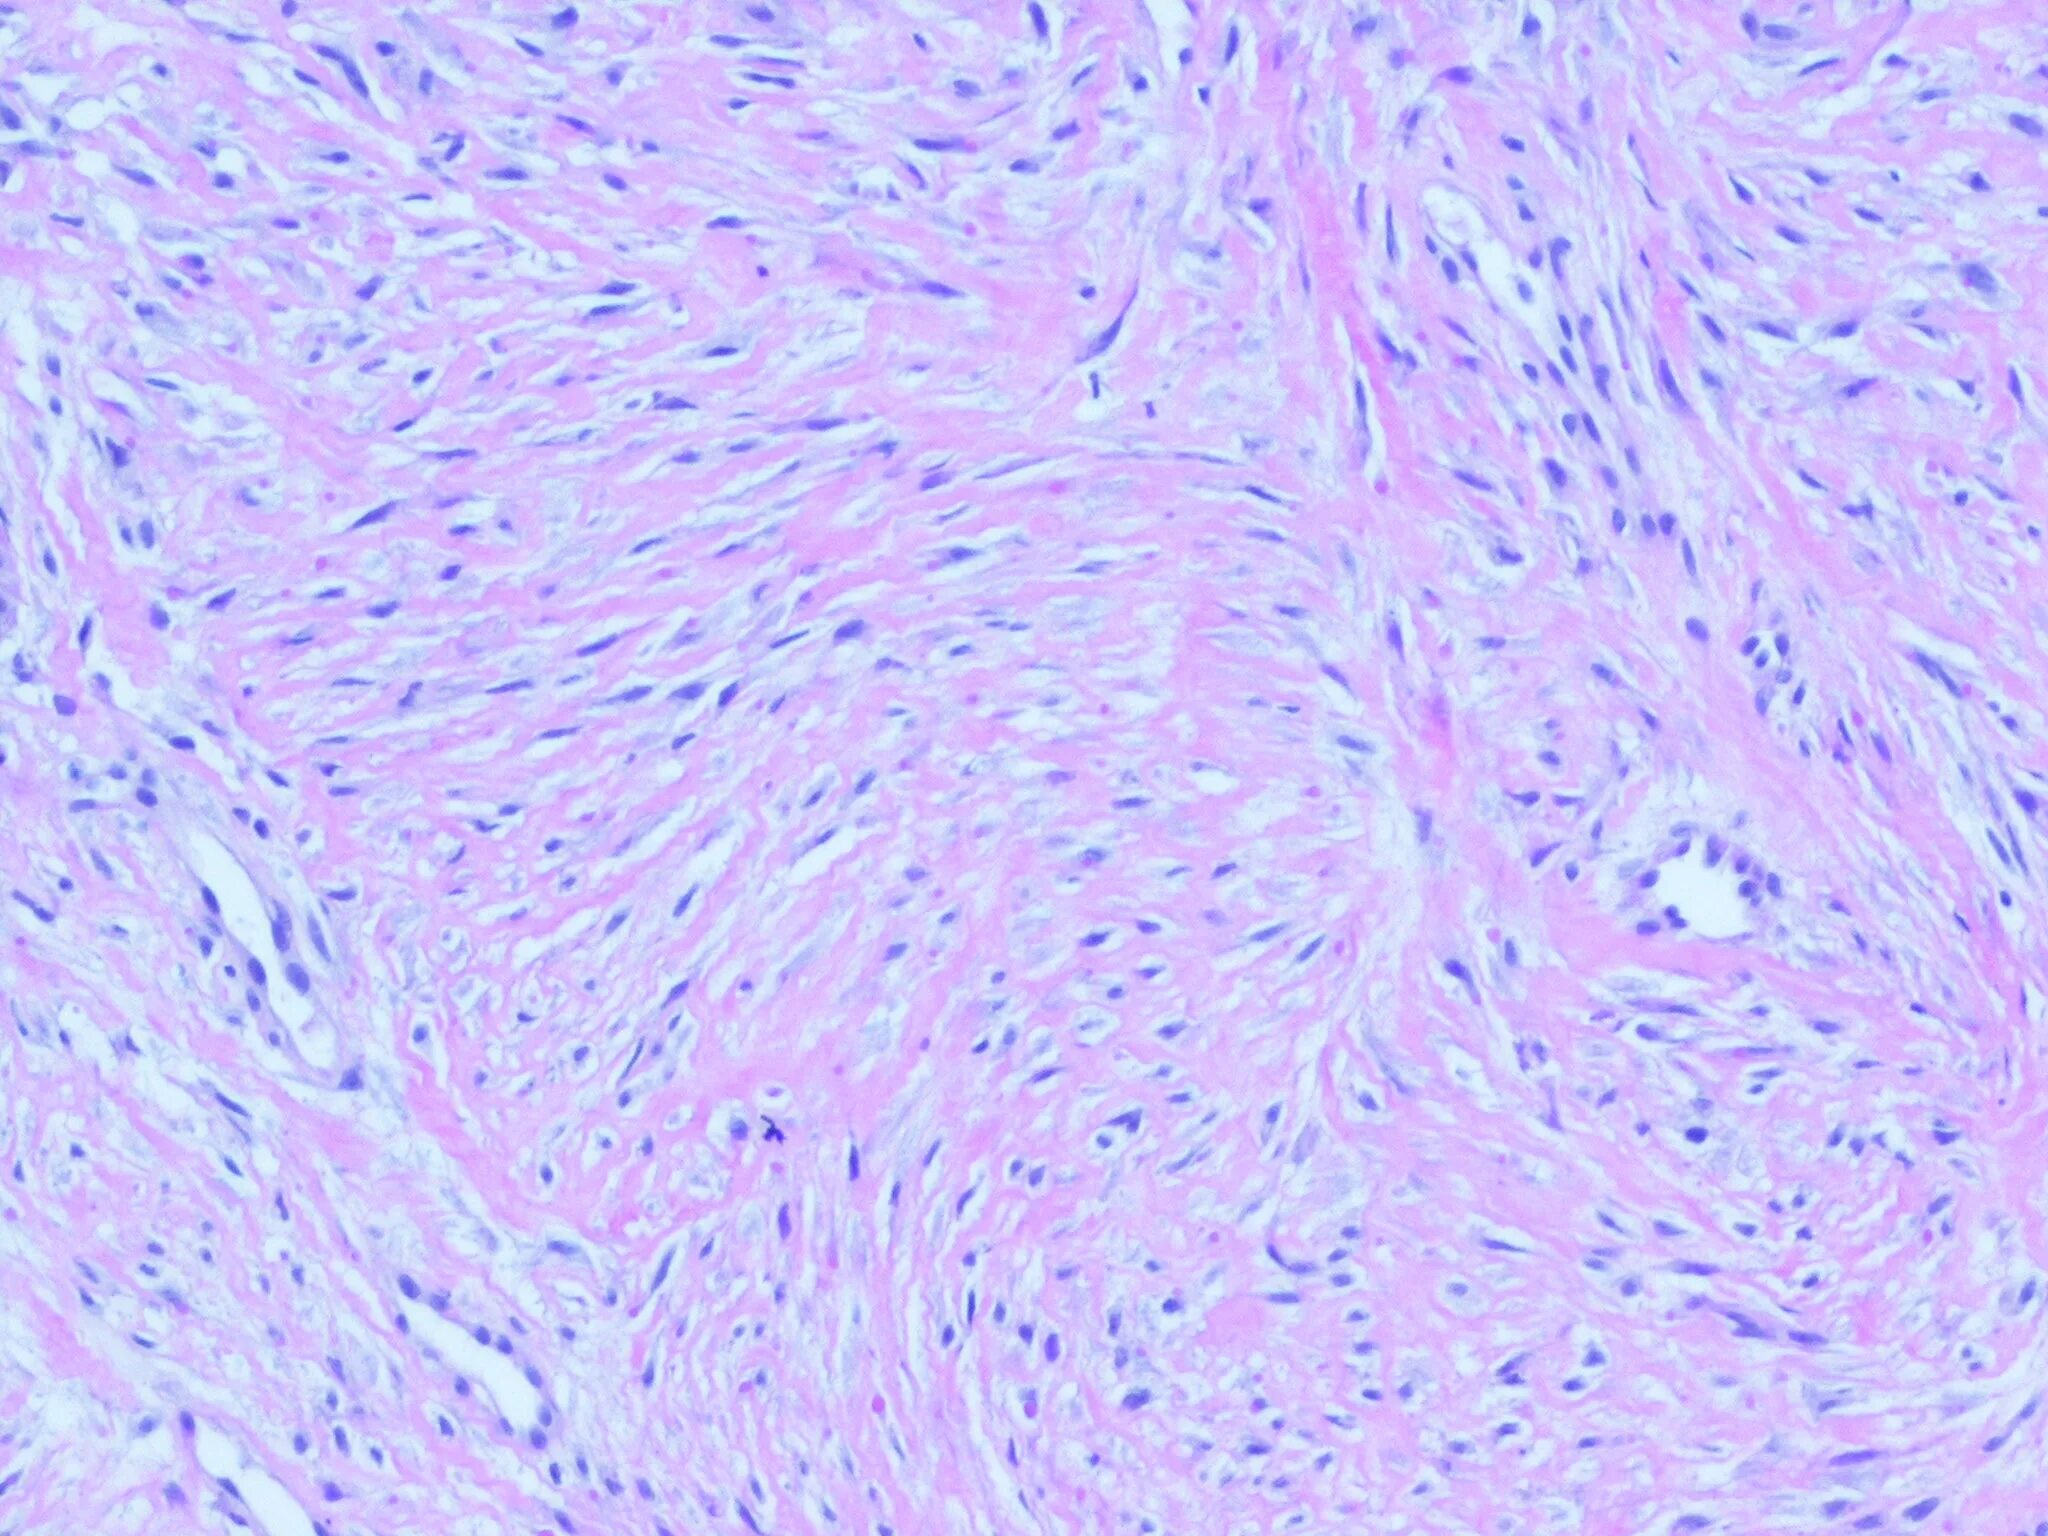

Фиброматоз мягких